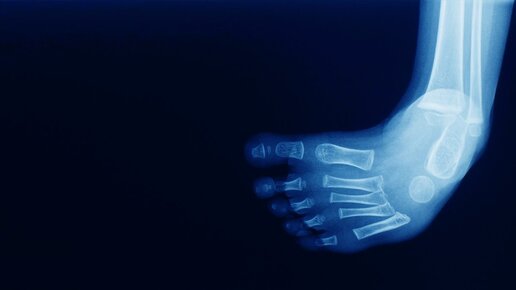

Многие дети ставят стопы пальцами внутрь, когда только учатся ходить. Но далее, с возрастом у большинства походка выравнивается. Что делать меньшинству, объясняет детский травматолог-ортопед клиники 100med Даниил Агафонов. Вопрос. Ребенок сильно заворачивает пальцы ног к стопе, при этом выворачивает стопы вовнутрь. Что это и что с этим делать? Ответ. То, о чем говорит читательница, в ортопедии называется «косолапие». Это распространенная аномалия развития костно-мышечной системы, которая, по статистике, чаще встречается у мальчиков, чем у девочек...

Косолапость у детей – это состояние, при котором ребенок несколько отклоняет ноги в стороны при ходьбе, напоминая медвежонка. Это наблюдается в основном у детей дошкольного возраста и закономерно может вызвать беспокойство у родителей. Почему же ребенок косолапит и что можно сделать, чтобы ему помочь? Одной из возможных причин косолапости у детей является физиологический фактор. Во время роста скелет у детей несколько нестабилен, поэтому в некоторых случаях дети могут немного отклонять ноги в стороны...